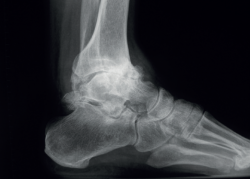

We must observe whether, in the lateral projections, there is an anterior translation of the talus, which often occurs in these chronic degenerative phenomena associated with instabilities (Figure 2).

Figure 2. Anterior translation of the talus, characteristic of tibiotalar arthropathies secondary to chronic instabilities.